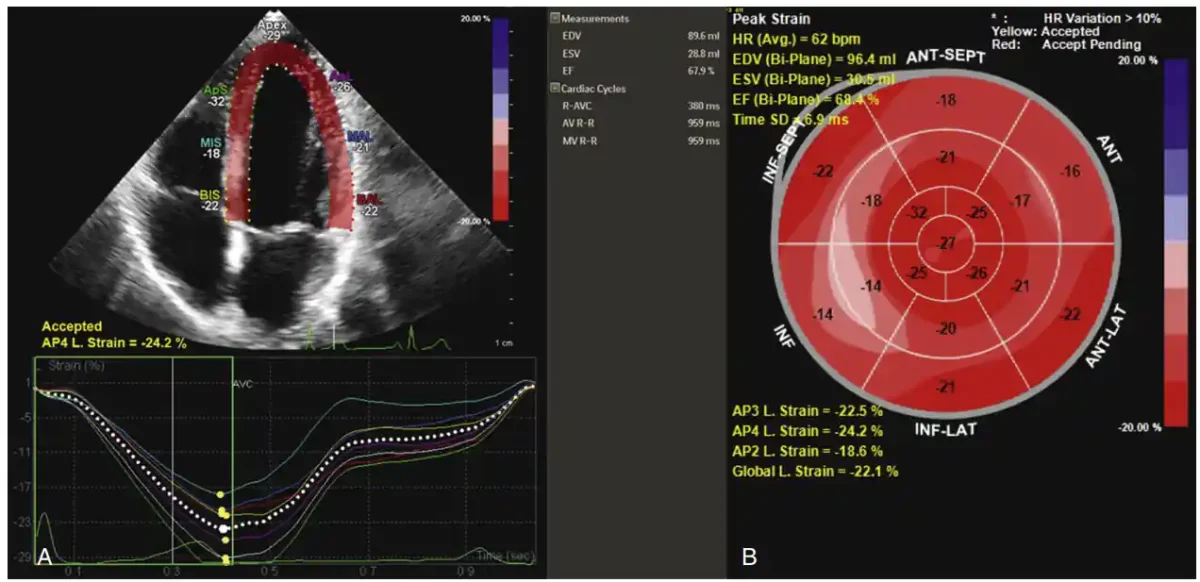

نمونه ای خروجی ماشین از اندازه گیری استرین (کرنش). تصویربرداری استرین با ردیابی لکه. نمای آپیکال چهارحفره‌ای از الگوی استرین طبیعی بطن چپ با نمایش رنگی (A) و نمودار ترکیبی چشم گاو (bull’s eye) متناظر (B) نشان می‌دهند که استرین طولی کلی (GLS) از نمای آپیکال لانگ اکسیس برابر –۲۲.۵٪، از نمای آپیکال چهارحفره‌ای برابر –۲۴.۲٪ و از نمای آپیکال دوحفره‌ای برابر –۱۸.۶٪ است، که میانگین استرین طولی –۲۲.۱٪ را می‌دهد و در محدوده نرمال قرار دارد.